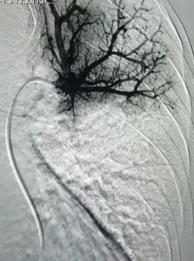

經(jīng)綜合評(píng)估并與家屬充分溝通后,局麻下行肺動(dòng)脈造影,提示左肺動(dòng)脈主干及左肺下葉動(dòng)脈閉塞,立即予以經(jīng)皮肺動(dòng)脈栓塞導(dǎo)管介入碎栓溶栓術(shù)。在心內(nèi)科韋鋒主任、郭良玉主治醫(yī)師及成婷護(hù)師的默契配合下,爭(zhēng)分奪秒順利完成手術(shù)。術(shù)后即刻復(fù)查肺動(dòng)脈造影示左肺動(dòng)脈主干及左肺下葉動(dòng)脈恢復(fù)血流,生命體征穩(wěn)定,指脈氧恢復(fù)至100%。經(jīng)過(guò)精心治療與護(hù)理,目前患者已康復(fù)出院。

術(shù)后肺動(dòng)脈血流恢復(fù)通暢